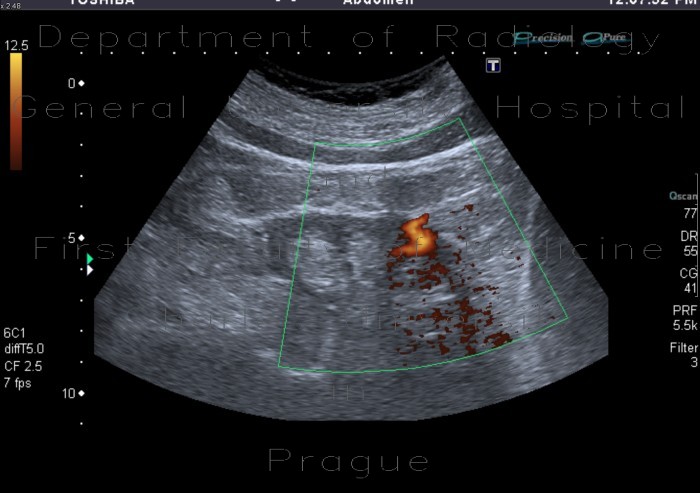

Arteriovenous malformation or AVM is an abnormal connection between veins and arteries, usually congenital. This pathology is widely known because of its occurrence in the central nervous system, but can appear in any location. An arteriovenous malformation is a vascular anomaly. It ... View Video

Arteriovenous malformation (AVM) is an abnormal connection between arteries and veins, bypassing the capillary system. This vascular anomaly is widely known because of its occurrence in the central nervous system, but can appear in any location. ... Read Article